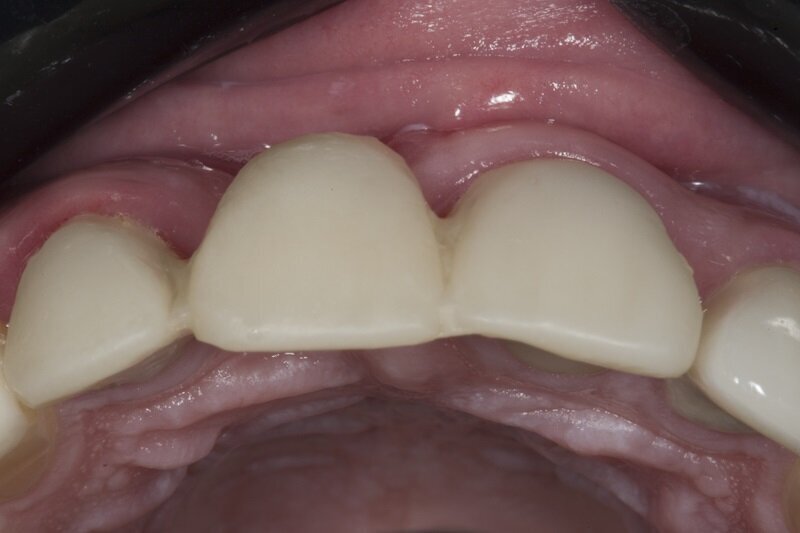

Po kolejnych 4 tygodniach wykonano zabieg bocznej regeneracji kostnej wyrostka zębodołowego w okolicy utraconego zęba 11 w przygotowaniu do przyszłej implantacji (Ryc. 9-11). Zastosowano biomodulację przy użyciu głowicy Genova, na rycinie 12 pokazano stan tkanek 3 tygodnie po zabiegu.

Ryc. 10_Zabieg regeneracji kostnej.

Ryc. 11_Zabieg regeneracji kostnej.

Ryc. 12_Zabieg regeneracji kostnej.